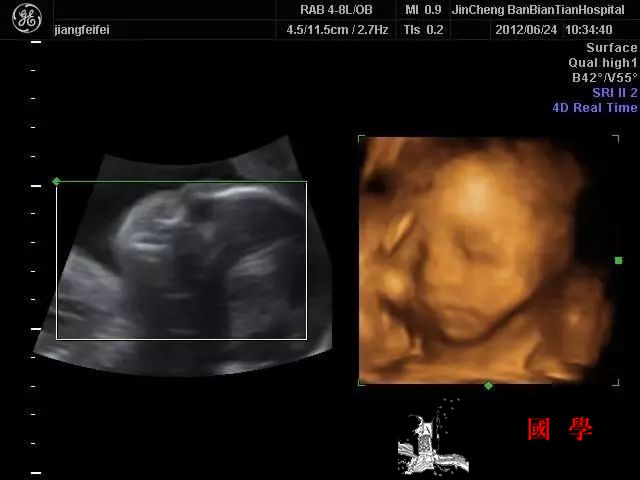

孕8周至孕5个月称为中敏期。此时是胎儿各器官进一步发育成熟的时期,对于药物的毒副作用较为敏感,但多数不引起自然流产,致畸程度也难以预测。此时是否终止妊娠应根据药物的毒副作用大小等因素,全面考虑后再作决定。继续妊娠者应在妊娠中、晚期做羊水、脐血、B超监测胎儿生长情况,了解鼻骨长度以及颈项皮肤厚度。若发现胎儿异常应予引产,若是染色体异常或先天性代谢异常,应视病情轻重及预后,及早终止妊娠或给予宫内治疗。孕5个月以上称低敏期。此时胎儿各脏器已经基本发育完全,对药物的敏感性较低,用药后不易出现明显畸形,但可出现程度不一的发育异常或局限性损害,如链霉素、卡那霉素、奎宁、奎尼丁可引起耳聋。